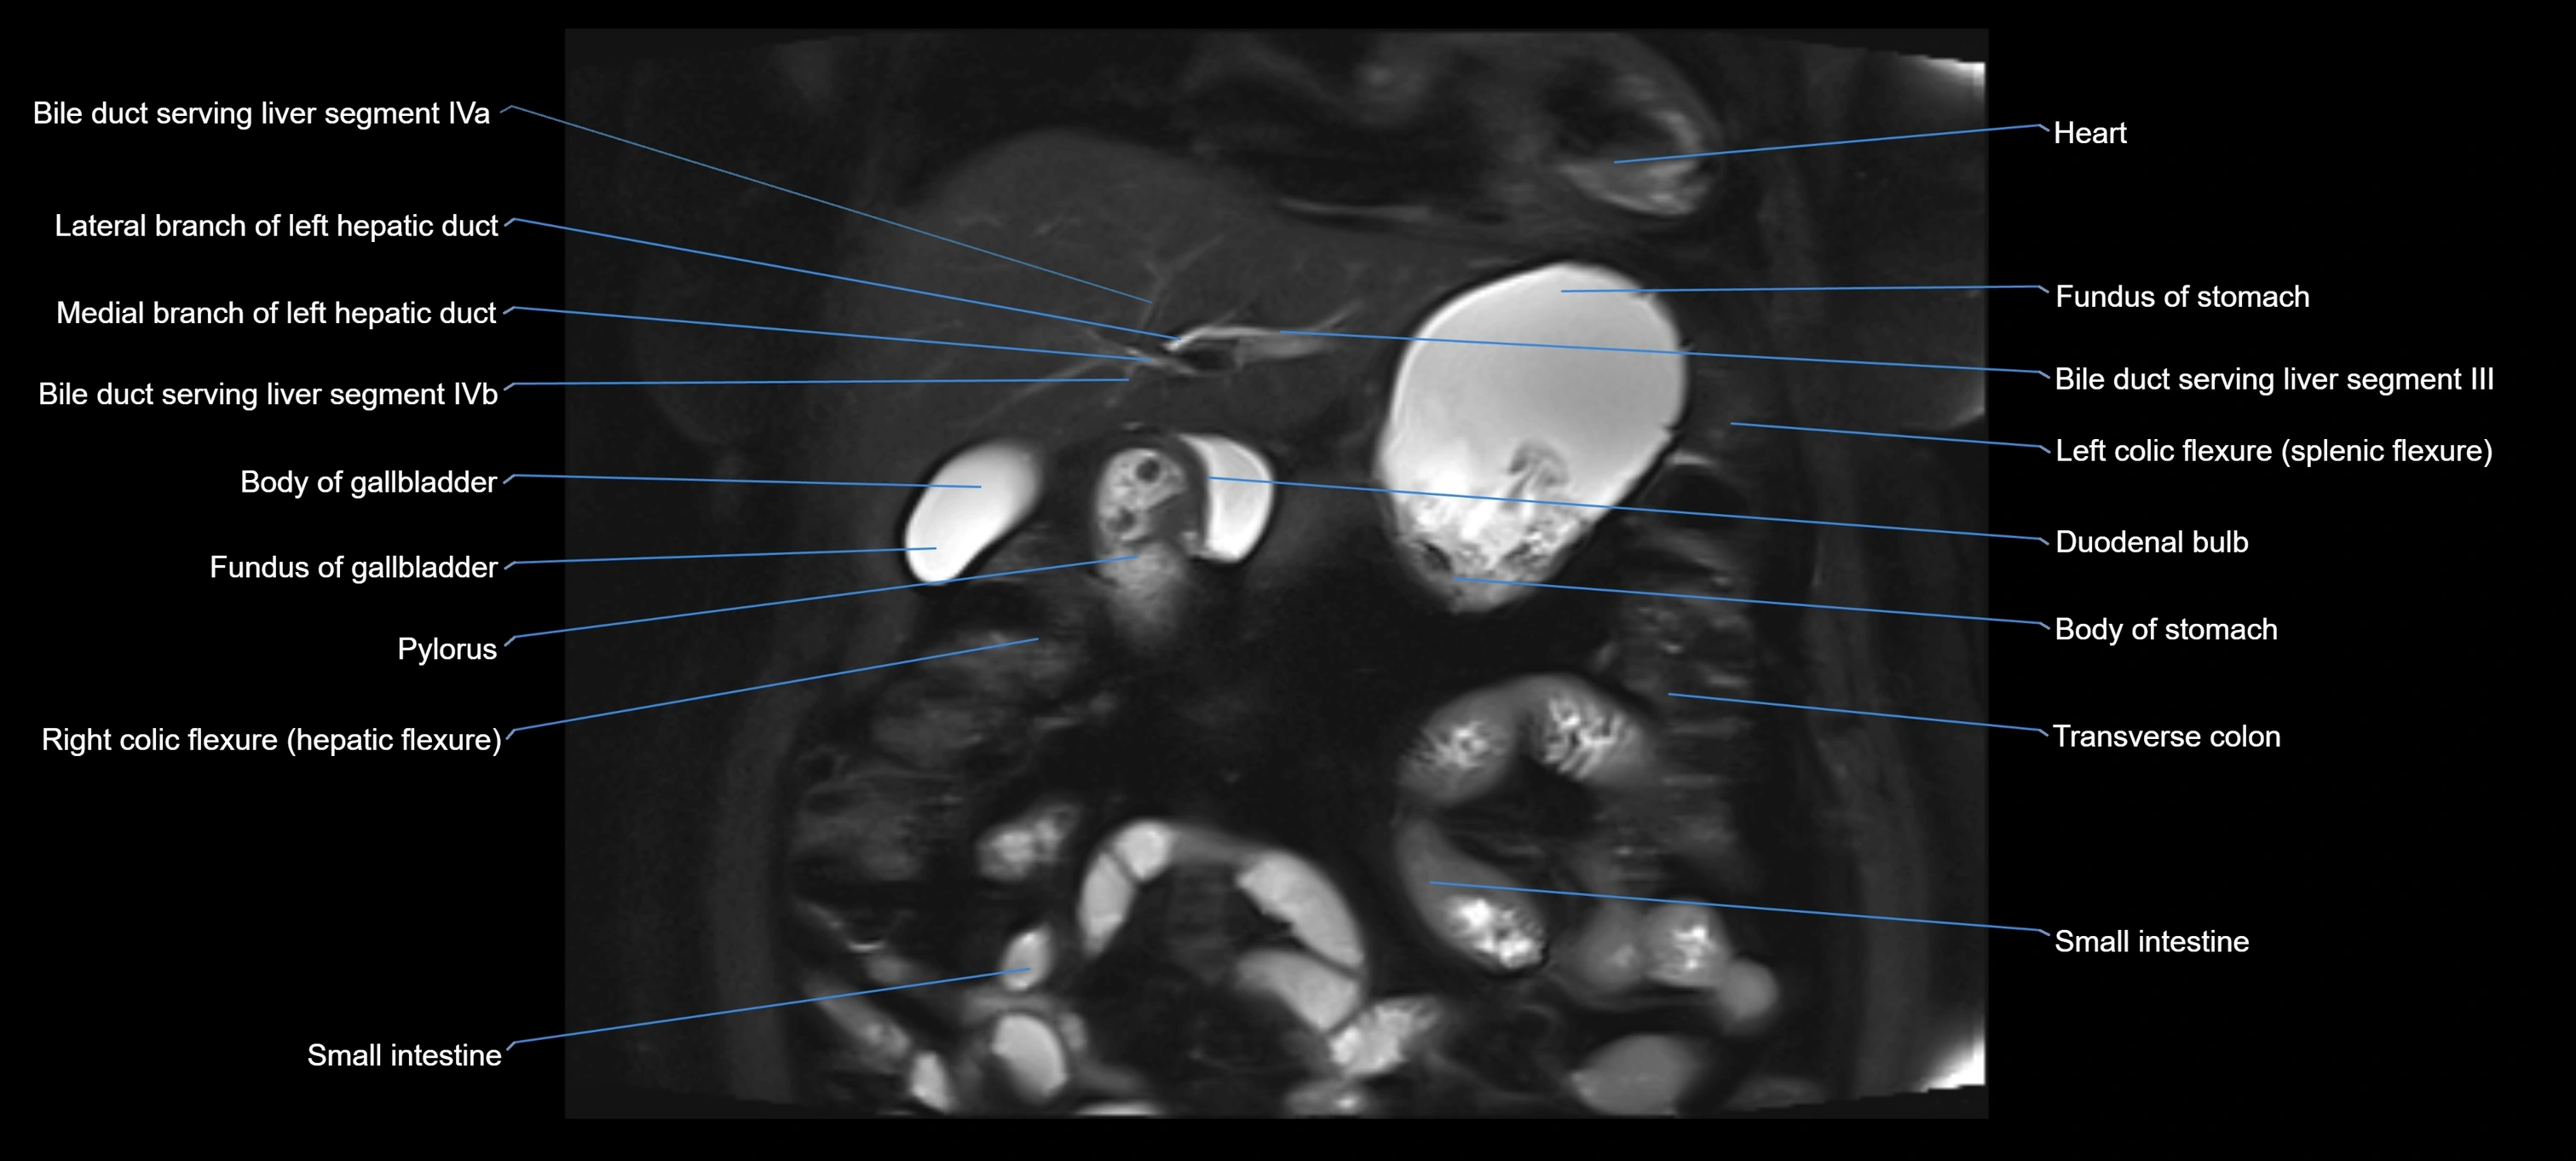

MRI image

image

Fullscreen Image